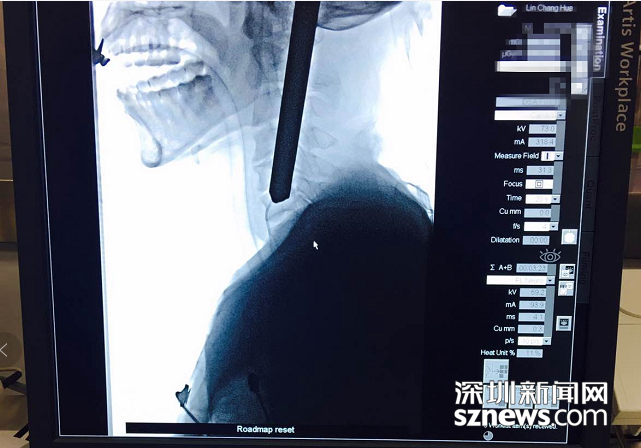

拍片顯示鋼筋深入患者頸部

北大深圳醫院接診后立即組織多學科會診,同時開通顱腦外傷綠色通道。消防員先行將傷者的顱外鋼筋切除,隨后,神經外科緊急行腦血管造影。考慮到鋼筋對大腦及腦血管可能造成的損傷,神經外科團隊決定立即為患者施行手術。